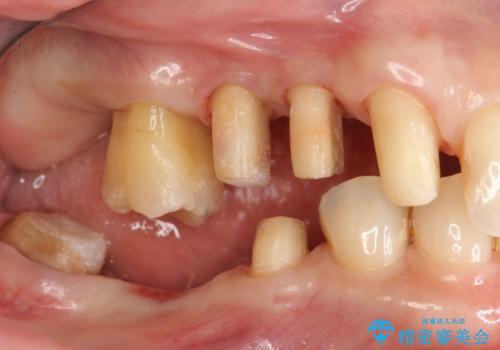

部分矯正を含む 歯周病治療 (再生治療・歯周ポケット除去・MTM・連結補綴)

- 歯のぐらつき、歯周病の検査を希望され来院されました。

検査の結果、強い歯ぎしりによる歯の周囲の骨の吸収が認められたため歯槽骨の再生・歯周ポケットの除去・力に対抗する連結補綴・補綴前処置としての小矯正を計画します。

特定の歯に強く力がかかりまた歯周病により臨床歯根が短くなっているような場合、歯の動揺を抑えるため連結補綴が検討されます。

歯の動揺が続くとより周囲の骨を失い最終的には歯を喪失してしまう可能性が高くなってしまうためです。